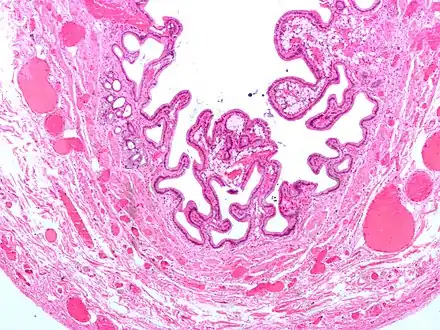

| Micrograph of cholesterolosis of the gallbladder, with an annotated foam cell. H&E stain. | |

The name strawberry gallbladder comes from the typically stippled appearance of the mucosal surface on gross examination, which resembles a strawberry. Cholesterolosis results from abnormal deposits of cholesterol esters in macrophages within the lamina propria (foam cells) and in mucosal epithelium. The gallbladder may be affected in a patchy localized form or in a diffuse form. The diffuse form macroscopically appears as a bright red mucosa with yellow mottling (due to lipid), hence the term strawberry gallbladder. It is not tied to cholelithiasis (gallstones) or cholecystitis (inflammation of the gallbladder).[2]